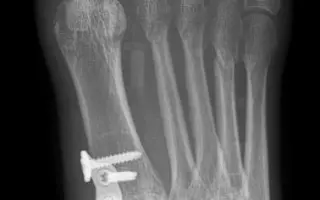

Další operace v prosinci

Moji milí a úžasní dárci. V prosinci mě čekají další dvě operace nohy, v pořadí to bude už šestá operace od roku 2021 a zdaleka ne poslední. Je to velká dřina, hodně to bolí, každá operace a narkóza si vezmou svoji daň. Ale vím, že jsou horší věci a neměnila bych, takže jedeme dál. Chtěla bych vám znovu všem strašně moc poděkovat. Opakuji se, ale Marťa, Andrejka, Donio a vy všichni, kdo jste mi přispěli a stojíte při mě, jste mi opravdu neskutečně pomohli a pomáháte ! Moc si toho vážím a jsem vám za to velmi vděčná.

Koncem března budu s operatérem na kontrole domlouvat detaily operace nohou a mou další komplikaci – alergii na kov, který se při této operaci aplikuje ve velkém a měl by tam zůstat trvale.